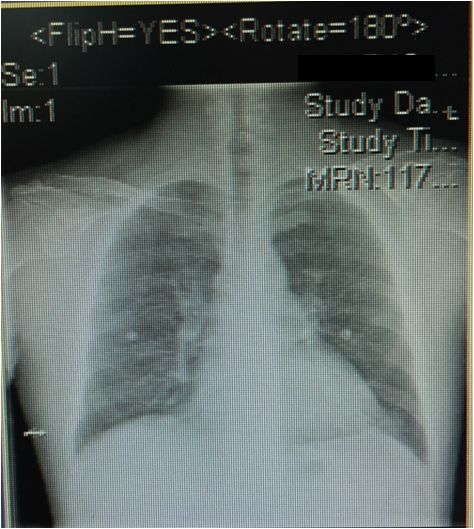

两肺纹理稍重,未见实变

主动脉结不宽,肺动脉段平直

心脏各房室不大

心胸比:0.52